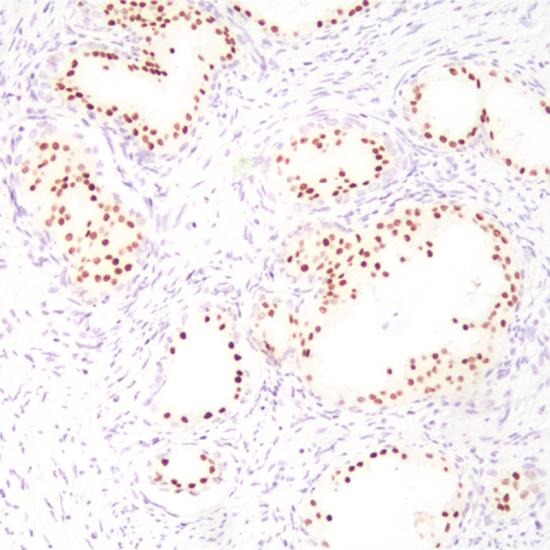

NKX3.1

NKX3.1抗體試劑(免疫組織化學(xué)法) 閩廈械備20200024號(hào)

• 陽(yáng)性部位:

細(xì)胞核

• 陽(yáng)性對(duì)照:

前列腺癌

NKX3.1基因位于染色體8p21.2,是一個(gè)生長(zhǎng)抑制子,能夠調(diào)節(jié)細(xì)胞凋亡、誘導(dǎo)抗氧化物產(chǎn)生和DNA修復(fù)的加強(qiáng)。NKX3.1是一種高度敏感和特異的前列腺癌標(biāo)記物,主要用于前列腺腫瘤的研究。